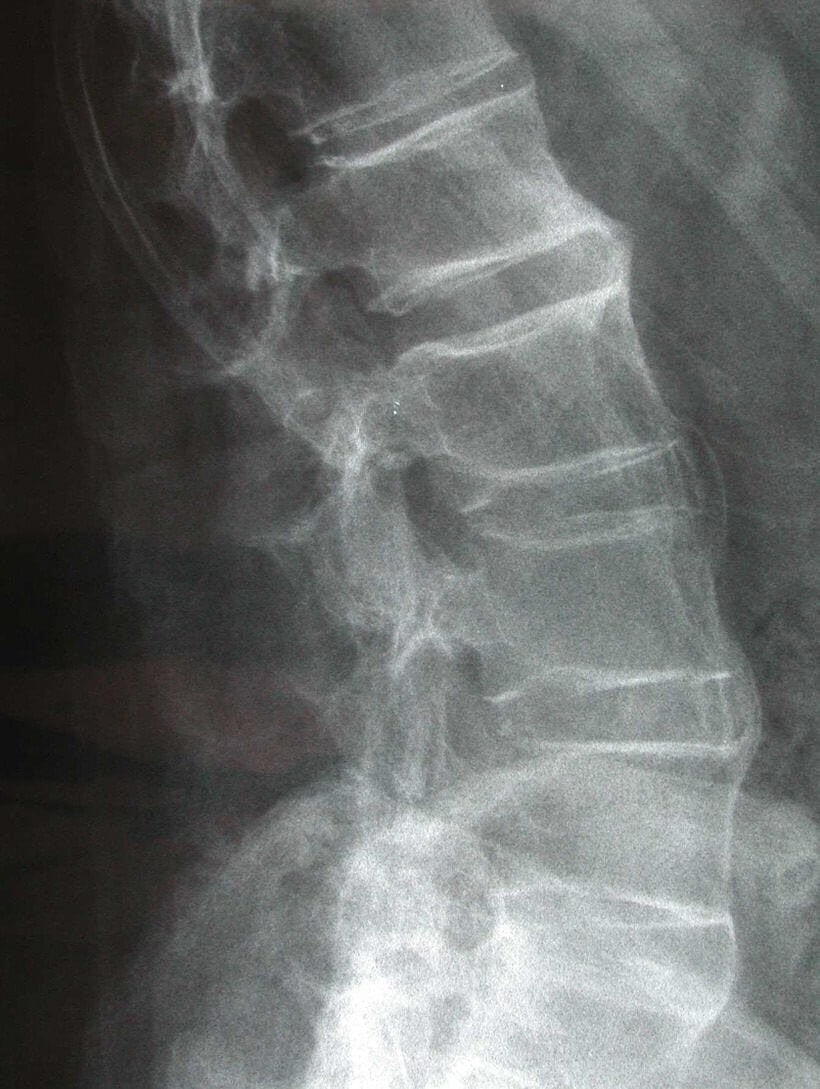

– Uram, ezek nem az ön felvételei… itt valami tévedés lesz…

– Ez egy gyerek gerince… a koponya és a csípőkép pedig…